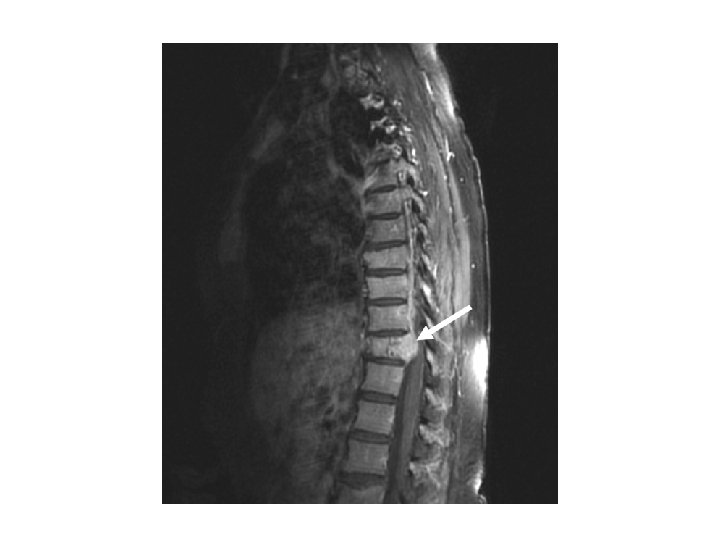

MRI of spinal cord compression in a women with past history of breast cancer